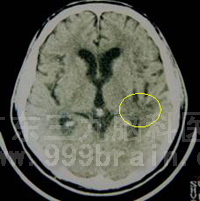

50岁的老王就是因为高血压引起突发脑出血昏迷被紧急送入广东三九脑科医院微侵袭神经外科救治的。入院行头颅CT检查见其左侧基底节区脑出血,出血量约为30ml。入院后,微侵袭神经外科 吴杰主任在详细了解其病情后,立即决定在局麻下为其行立体定下钻孔引流术,手术只花了30分钟,术程顺利,术后老王的神智得以明显改善。术后半个月复查CT检查见老王颅内血肿已基本消失,经过肢体功能锻炼,老王康复如常人,肢体运动功能没有因此受到影响。目前已康复出院。

术前CT示左基底节区脑出血急性期。 立体定向下行钻孔引流术。